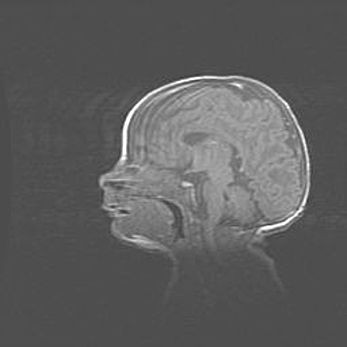

Наружная гидроцефалия с возможной атрофией височных областей.

Возраст: 28 дней

Вес: 3670 г

Пол: мужской

Окружность головы: 38 см

Срок гестации: 40 недель

Гидроцефалия головного мозга у новорожденных – это заболевание, которое характеризуется скоплением избыточного количества спинномозговой жидкости в желудочковой системе головного мозга в результате затруднения её перемещения от места выработки к месту поглощения в кровеносную систему или вследствие нарушения абсорбции. При открытой наружной форме гидроцефалии у новорожденных расширяются и переполняются субарахноидные пространства.

При нормотензивных  формах,  которые,  как  правило,  являются  следствием  перенесенных ишемических  повреждений  паренхимы  мозга,  возможно  сочетание микроцефалии  с нормотензивной гидроцефалией. В основе данных изменений лежит атрофия больших полушарий с преимущественной  локализацией  в  лобно-височных  областях.